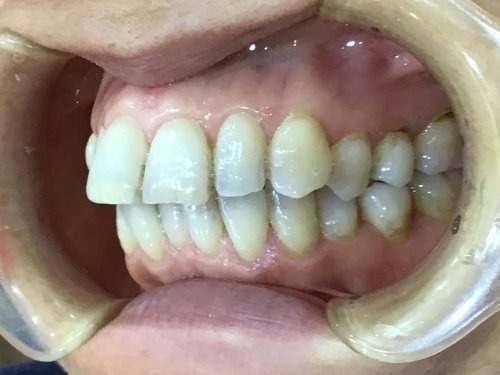

左横